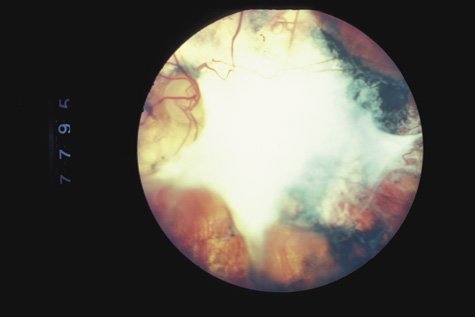

Retinitis sclopeteria is the rupture of the choroid or retina caused by shock waves generated by passage of a high-velocity missile through the orbit without directly striking the eye. Initially a subretinal or vitreous hemorrhage is seen. If the optic nerve is damaged, visual acuity can be profoundly decreased. In severe cases, massive amounts of fibrous tissue proliferate into the eye (Fig. 27). In others, as the blood clears, a claw-like break is often seen in Bruch's membrane and in the choriocapillaris (Fig. 28). Retinal detachment rarely occurs at the site of the injury, probably because of binding of the retina to the choroid by fibrous tissue, but late detachment from a break at a distal site can occur.97,98

Fig. 27. A: the left eye of a man who shot himself with a pistol. The bullet passed through both orbits, behind the globes. The optic nerve is at the left of the photograph. There is extensive fibrous proliferation. B: The right eye has considerably less retinal damage, but the visual acuity is hand movements because of optic atrophy.